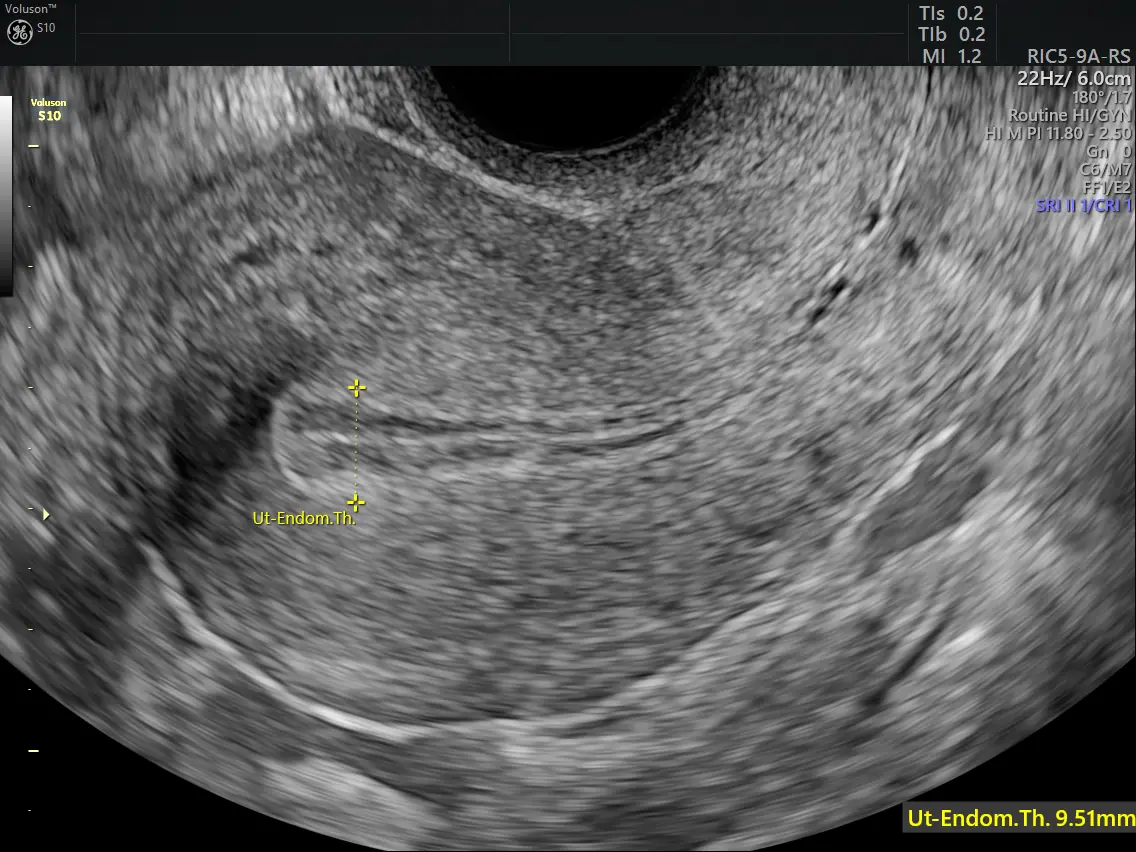

Diagnosis begins with a detailed medical history and evaluation of menstrual patterns. Pelvic ultrasound is commonly used to measure endometrial thickness and detect abnormalities.

If abnormal thickening is suspected, an endometrial biopsy is performed to examine the tissue under a microscope. This step is crucial in identifying whether atypical cells are present and determining the appropriate treatment plan.